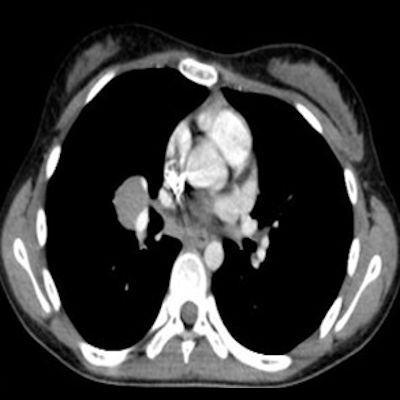

14 yaş, K

Baş ağrısı ve sağda abdusens felci

Neurosarcoidosis manifesting as cavernous sinus syndrome in systemic sarcoidosis

Sağ kavernoz sinüste kontrastlanan ICA yı çevreleyen daraltan yumuşak doku değerleri mevcuttur.Sağ parahiler bölgede lenfadenopati veya kitle lezyonu ile uyumlu olabilecek görünüm mevcuttur.Ayırıcı tanıda Nazofarink Ca metastazı,lenfoma,sarkaidoz,wegener granulomatozu düşünüle bilir.Çocuk hasta olduğu için daha çok lenfoma olarak düşündüm